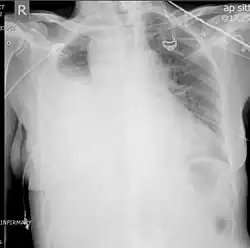

Chest X-ray

Two chest X-rays: left showing a massive left-sided hemothorax; right showing a massive right hemothorax

A chest X-ray is the most common technique used to diagnosis a hemothorax.[23] X-rays should ideally be taken in an upright position (an erect chest X-ray), but may be performed with the person lying on their back (supine) if an erect chest X-ray is not feasible. On an erect chest X-ray, a hemothorax is suggested by blunting of the costophrenic angle or partial or complete opacification of the affected half of the thorax. On a supine film the blood tends to layer in the pleural space, but can be appreciated as a haziness of one half of the thorax relative to the other.[5] A small hemothorax may be missed on a chest X-ray as several hundred milliliters of blood can be hidden by the diaphragm and abdominal viscera on an erect film. Supine X-rays are even less sensitive and as much as one liter of blood can be missed on a supine film.[24]